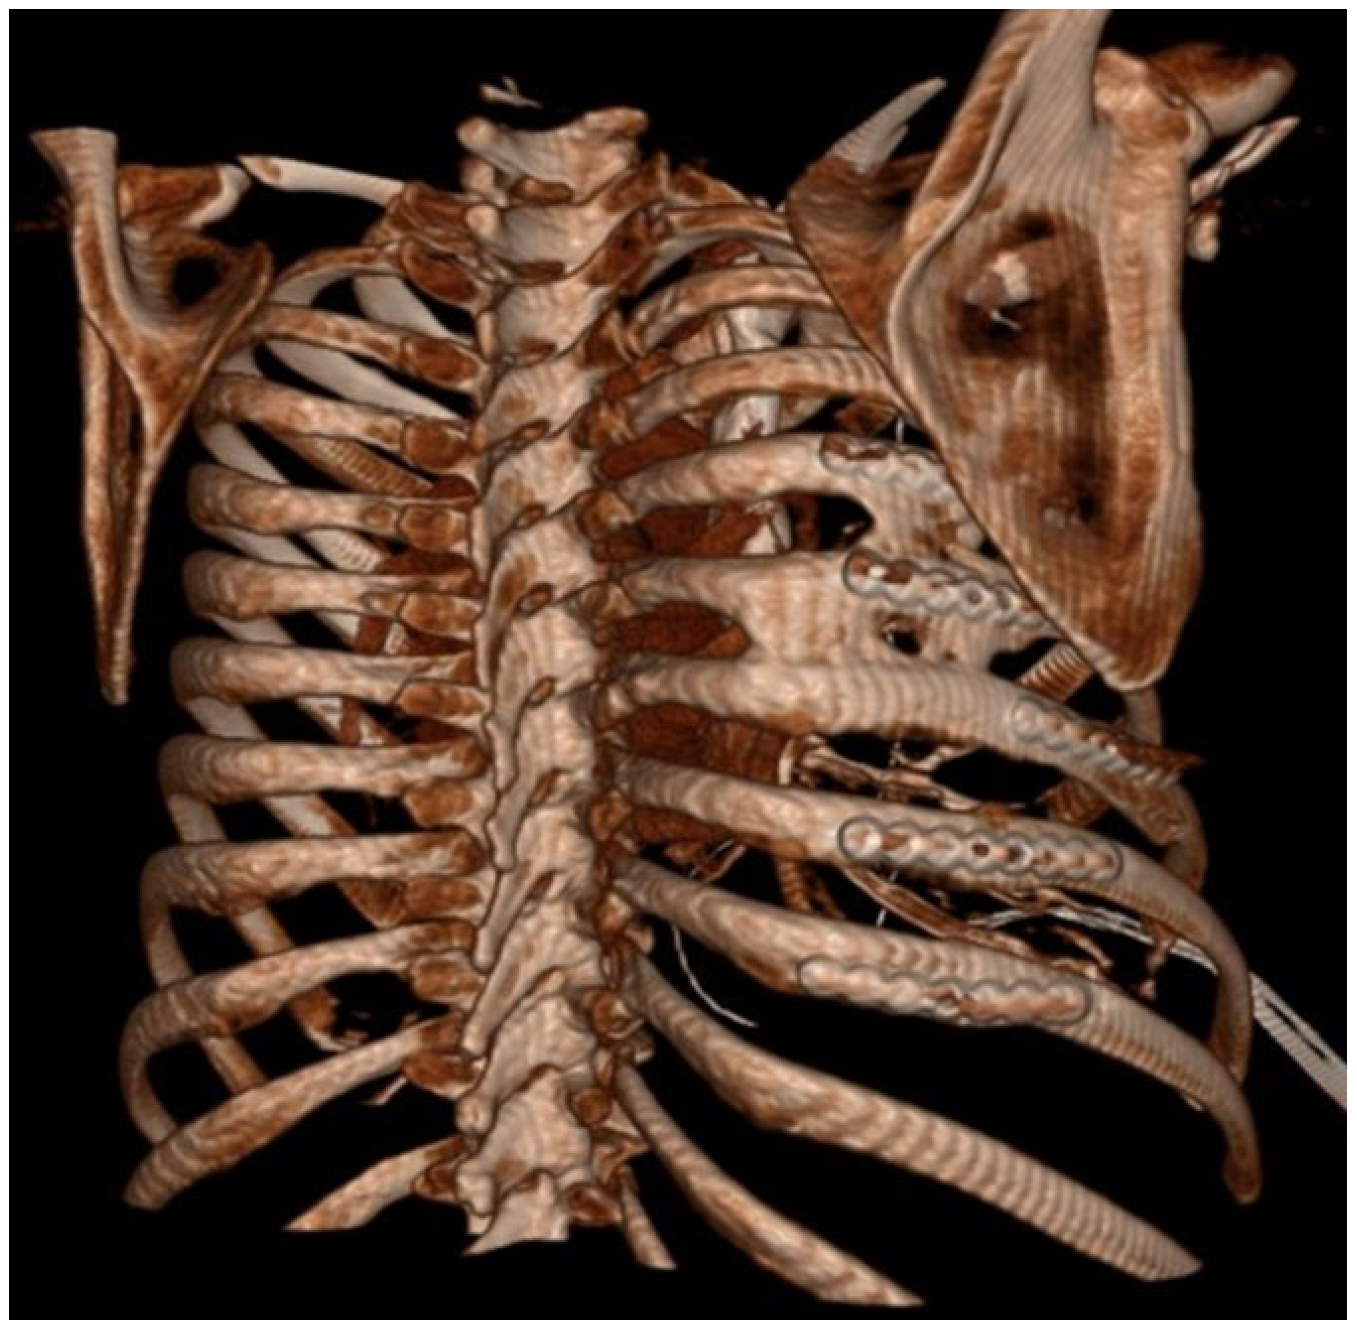

Figure 1. Chest X-ray showing HO at the tips of the red arrows.

HO was noted in nine patients (43%) and seen as early as 8 months post-operatively. Overall, 15% (32/208) of rib fractures showed evidence of HO at follow-up. In patients that developed HO, 36% (32/88) of rib fractures had evidence of HO formation. The HO was evident on posterior–anterior chest X-ray in 25% (2/8) of patients. No significant difference was noted in patients with HO when accounting for gender (43.8% vs. 56.3%, p = 0.647), ISS (24 ± 12 vs. 18 ± 9, p = 0.265), flail chest injury (36.4% vs. 63.6%, p = 0.425), number of fractures (8 (4–16) vs. 9 (3–21) p = 0.917), polytrauma (44% vs. 50%, p = 0.801),time to follow-up CT scan (18.0 (7.7–88.5) vs. 14.2 (7.1–56.7) p = 0.247), or number of SSRF plates (4 (3–11) vs. 5 (3–11) p = 0.862). The number of patients with traumatic brain injury was similar, with three patients in both groups. A significant difference in these patients was identified when comparing approach to screw fixation pre-drilling with self-tapping (ST) screws versus self-drilling (SD) screws (89% vs. 11%, p = 0.024), year of operation (2107 ± 1.9 vs. 2020 ± 1.7, p = 0.004), and operative day (6 (0–9) vs. 2 (2–5), p = 0.023). All patients were treated with non-steroidal anti-inflammatory medications after injury (ibuprofen). The difference in patients with HO and the difference in types of screws used are illustrated in Figure 3.